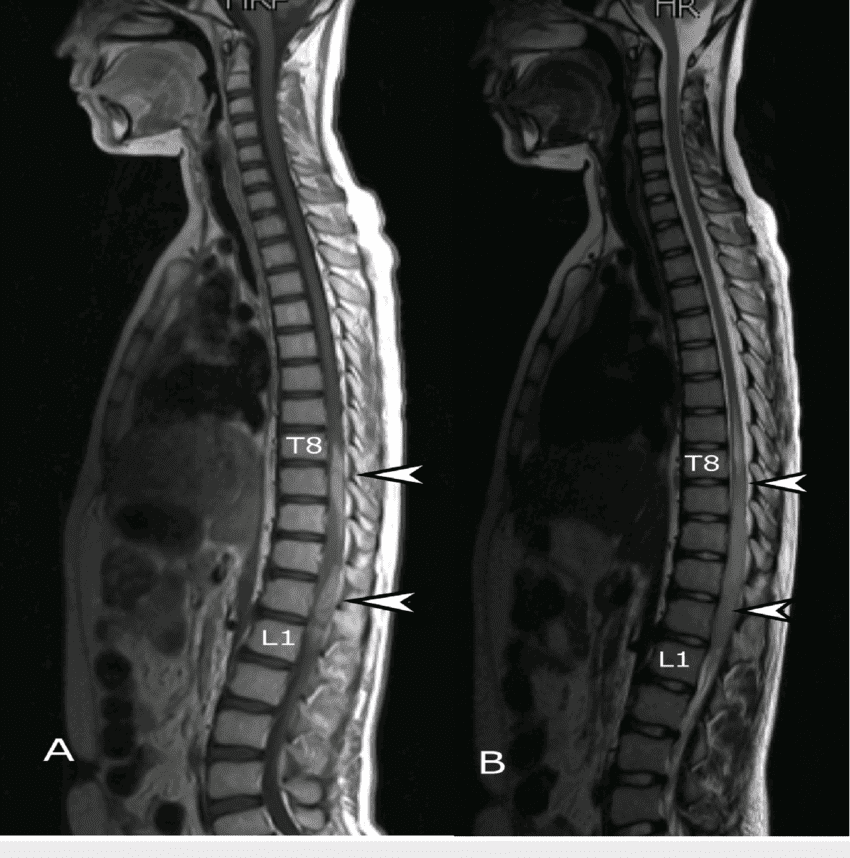

МРТ при шейном остеохондрозе назначается крайне редко, но исследование проблем в грудном отделе чаще всего требует применения этого метода. Его основным преимуществом является то, что на снимках четко видны не только нарушения в структуре скелета, но и патологические процессы в мягких тканях.

На МРТ снимках остеохондроза можно увидеть характер нарушений хрящевой ткани, а также основную направленность заболевания. Преимуществами такого метода являются следующие достоинства: